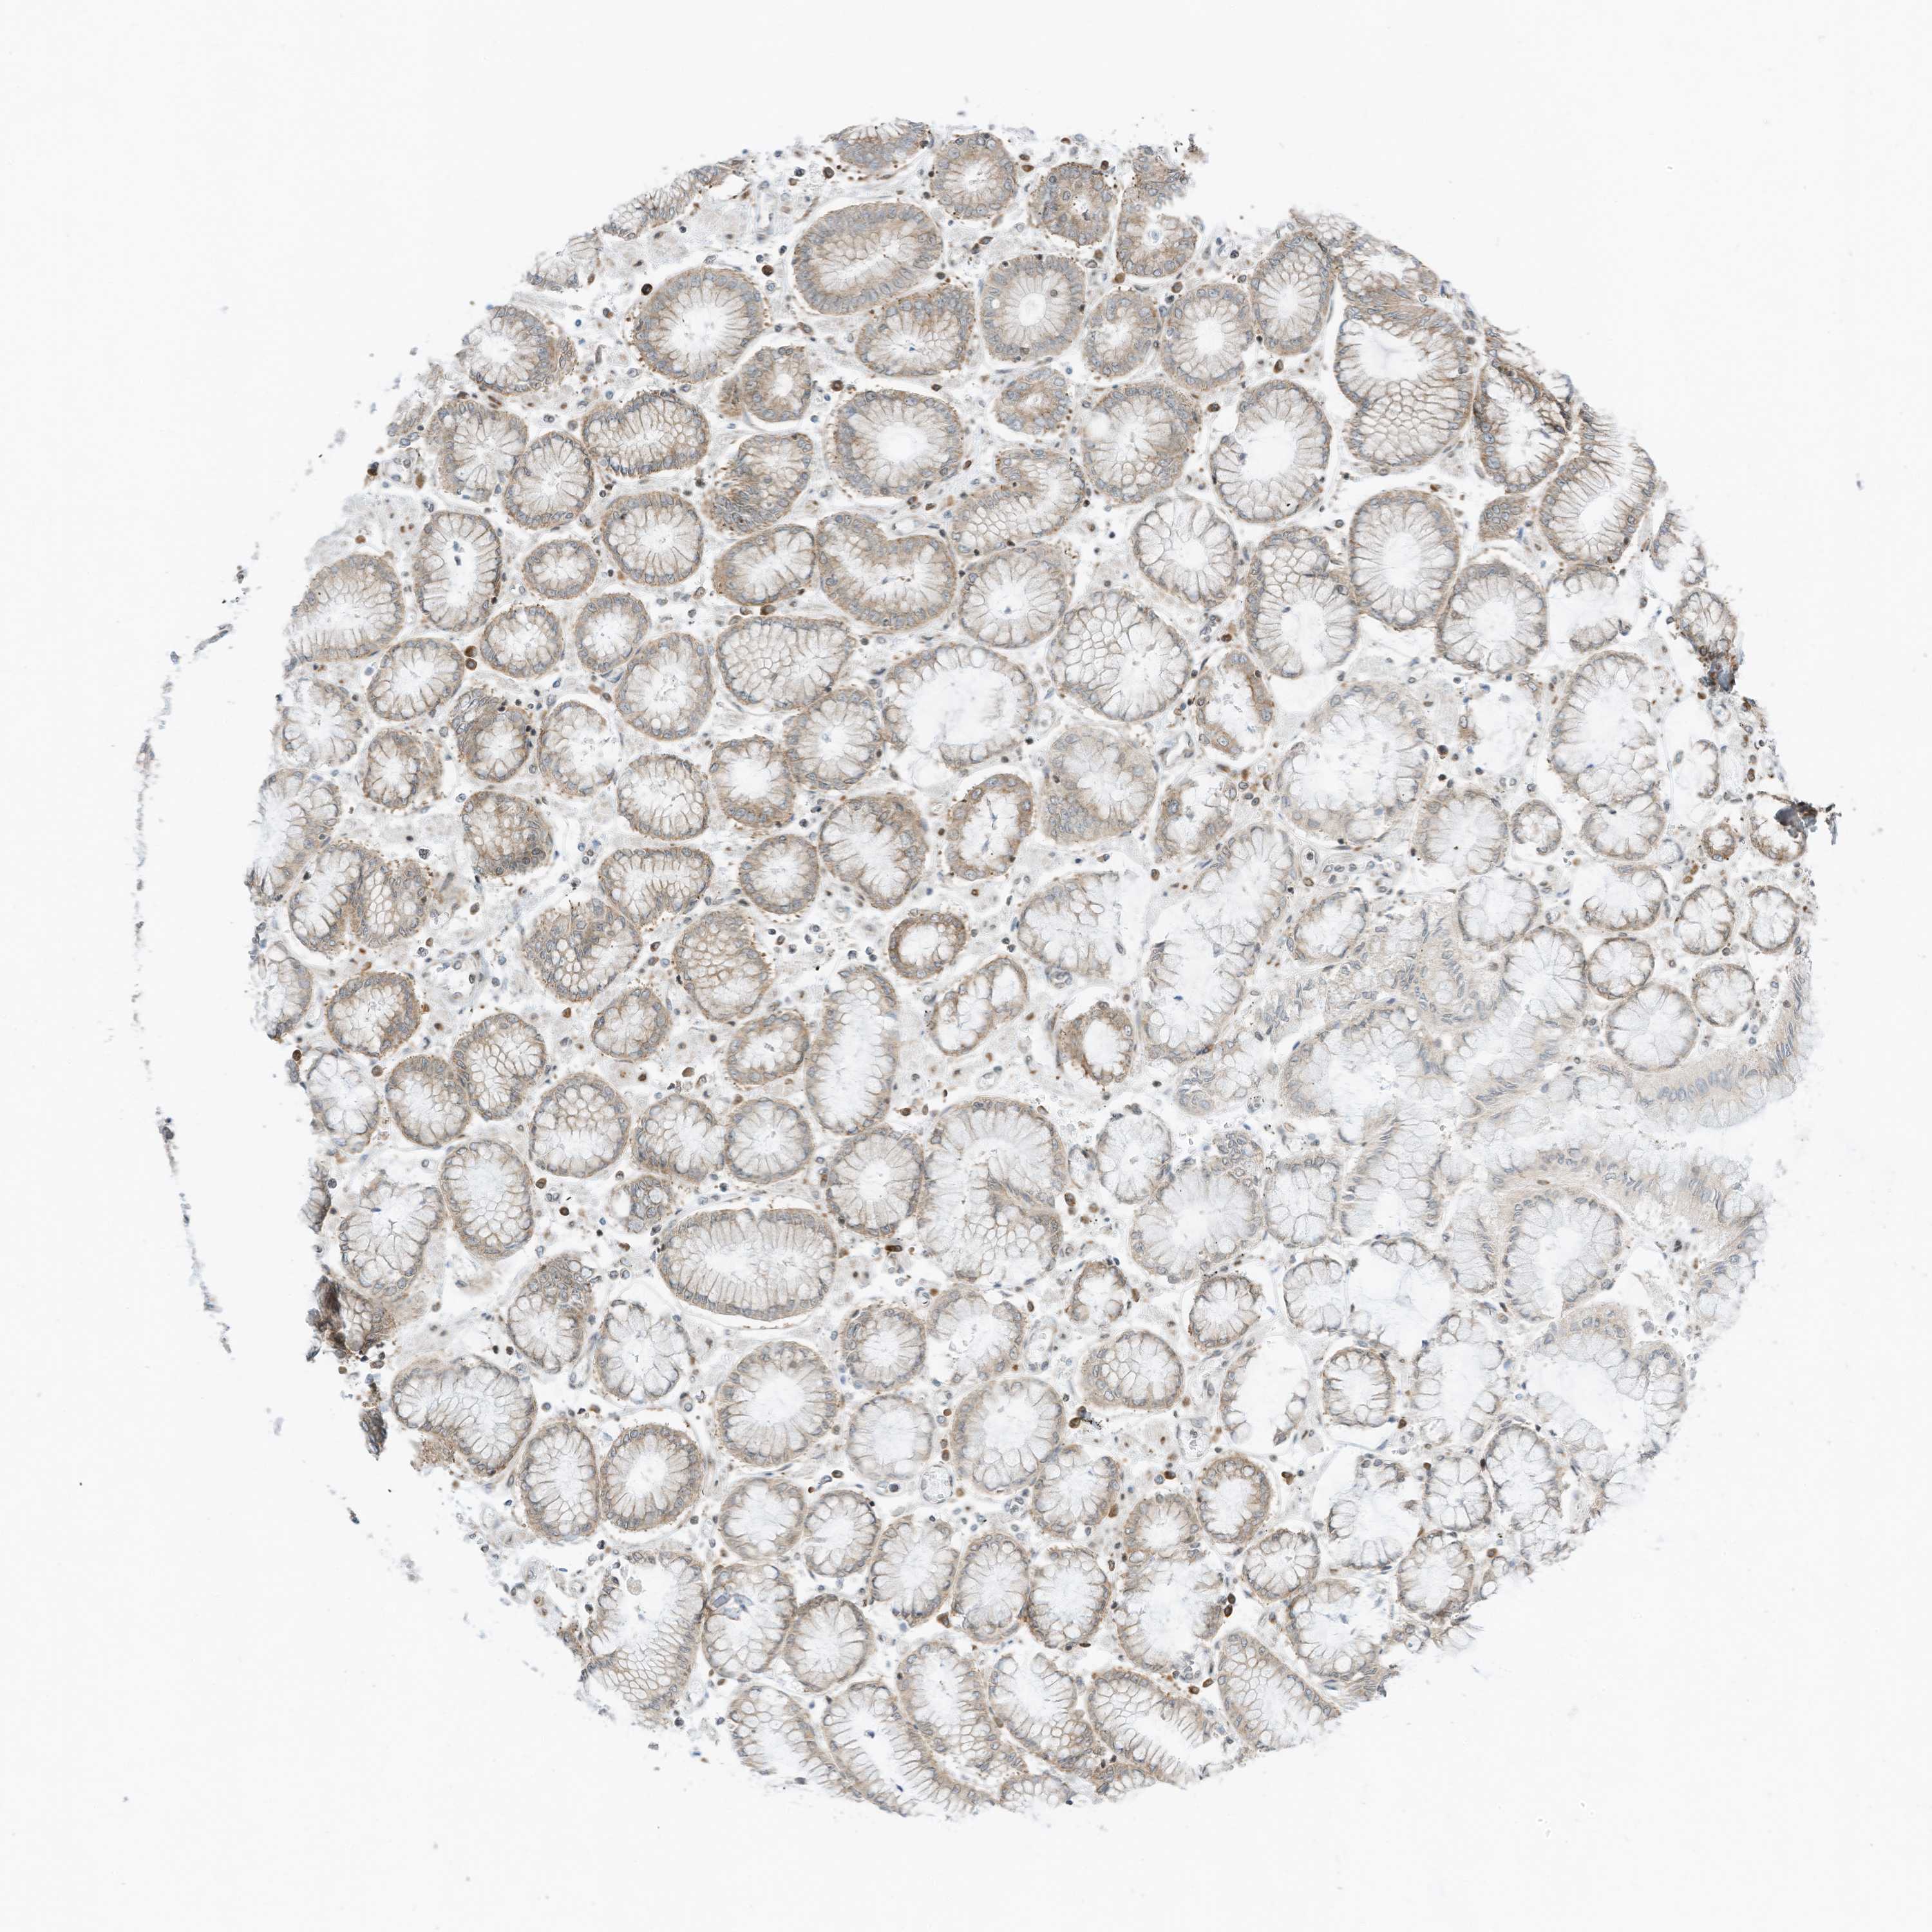

STOMACH CANCER - Protein expressioni

A mouse-over function shows sample information and annotation data. Click on an image to view it in a full screen mode. Samples can be filtered based on level of antibody staining by selecting one or several of the following categories: high, medium, low and not detected. The assay and annotation is described here.

Note that samples used for immunohistochemistry by the Human Protein Atlas do not correspond to samples in the TCGA dataset.

Antibody stainingi

Antibody staining in the annotated cell types in the current human tissue is reported as not detected, low, medium, or high, based on conventional immunohistochemistry profiling in selected tissues. This score is based on the combination of the staining intensity and fraction of stained cells.

Each image is clickable and will lead to virtual microscopy that enables deeper exploration of all samples and also displays staining intensity scores, fraction scores and subcellular localization as well as patient and tissue information for each sample.

Antibody HPA035642

Staining

High

Medium

Low

Not detected

Intensity

Strong

Moderate

Weak

Negative

Quantity

>75%

75%-25%

<25%

None

Location

Nuclear

Cytoplasmic/membranous

Cytoplasmic/membranous,nuclear

Adenocarcinoma, NOS